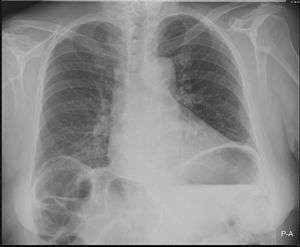

Chest X-ray showing obvious Chilaiditi's sign, or presence of gas in the right colic angle between the liver and right hemidiaphragm. | |

Chilaiditi syndrome is a rare condition when pain occurs due to transposition of a loop of large intestine (usually transverse colon) in between the diaphragm and the liver, visible on plain abdominal X-ray or chest X-ray.[1]

Normally this causes no symptoms, and this is called Chilaiditi's sign. The sign can be permanently present, or sporadically. This anatomical variant is sometimes mistaken for the more serious condition of having air under the diaphragm (pneumoperitoneum) which is usually an indication of bowel perforation, possibly leading to surgical interventions.